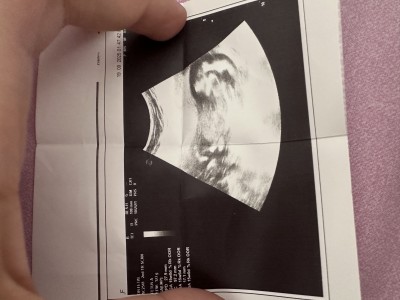

Gebelik Hakkında Yapılacak Tahminler Nelerdir?

Tahmin yaparmisiniz

Gebelik haftası

17

İsim tavsiye veya cinsiyet tahmini gibi soruların sohbet alanında sorulması gerekmektedir. Menüden gebelik dışı konular için ayrılmış alanda konunuzu açabilirsiniz..